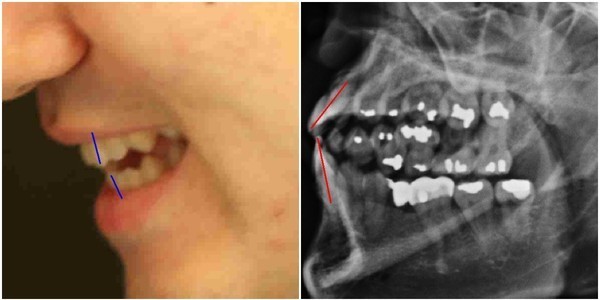

이헌 변호사는 문씨가 검찰 진술에서 일반적인 의료상식과 다르게 아말감 치료가 일반적이라고 극구 주장하고 있는 점과, 무려 16개의 치아를 아말감으로 치료하고, 브릿지와 임플란트 치료까지 했다면서도, 가장 기본적인 파노라마 사진을 찍지 않았다고 진술한 사실을 지적하면서, 문씨의 진술 및 제출 증거에 강한 의문을 나타냈다.‘유령건강보험증 번호’ 의혹의 출발점이라 할 수 있는 주신씨의 치아 X-Ray(이하, 구외 X-Ray)사진은, 양 박사와 치과의사 김우현씨 등이 주신씨의 대리신검 의혹을 제기한 주요 근거 중 하나였다.

주신씨의 구외 X-Ray는 그가 허리 MRI를 촬영하면서 같이 찍은 X-Ray 사진들 중에서 치아가 보이는 X-Ray 사진이다.

따라서 구외 X-Ray 상에 나타나는 각종 의혹은, 허리 MRI와 더불어 해당 피사체가 주신씨가 아닐 가능성에 무게를 더한다.

주신씨 구외 X-Ray 사진을 보면, 치아 상태가 매우 불량하다는 사실을 알 수 있다.

치아 2개는 아예 없고, 아말감으로 때운 치아가 무려 14개에 달한다.아말감(Amalgam) 치료는 여러 가지 단점을 갖고 있어 사용빈도가 크게 줄고 있다는 것이 치과의료계의 공통된 평가다.

서울 방배동에 사는 중산층 청년이, 치과의사는 물론 환자들도 기피하는 아말감을 이용한 치과 치료를 이처럼 많이 받았다는 것은, 쉽게 받아들이기 어렵다는 것이 이들의 지적이다.

더욱 의심이 가는 부분은 주신씨의 경우, 하악 좌측 1소구치(아래쪽 좌측 첫 번째 작은 어금니)까지 아말감으로 치료했다는 사실이다.

그러나 이런 경우는 매우 드물다는 것이 치과의사들의 일반적인 견해다.

치과의사 김우현씨는, 주신씨의 영구치가 맹출을 시작했을 것으로 추정되는 1990년대 중반 이후, 젊은 사람이 1소구치들을 포함한 구치부 치아 전체를 아말감으로 치료했다고 보기엔 무리가 있다고 지적했다.

치의학 박사 C씨는 뉴데일리와 기자와의 인터뷰에서 “주신씨의 전체적인 치료 상태를 보면, 소위 말하는 야매로 했을 가능성이 높다”고 밝혔다.

“(주신씨의 것이라고 알려진 구외 X-Ray 사진을 보면) 최근 국내에서 교육받은 치과의사의 치료라고 생각할 수 없을 정도”

“(주신씨 구외 X-Ray 사진 상의) 45번, 46번 보철치료 및 치아 상실 문제도 마찬가지다. 보철물로는 상당히 저렴한 비귀금속 합금을 사용한 것으로 보인다. 37번 치아는 아예 없는 상태로 방치하기도 했다”

“박주신씨의 가정환경을 고려하면, 이런 치료를 받았을 가능성은 1%도 안 된다. 서울 방배동에 거주했던 중산층 이상의 가정에서는 흔치 않은 상황”